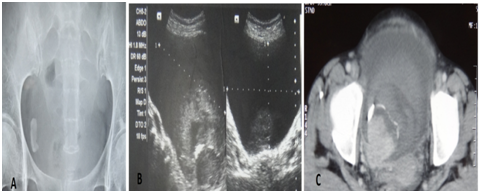

A 45years old non hypertensive married female was referred to us with the complaints of dysuria and vague lower abdominal discomfort since last 4months and was diagnosed elsewhere as a case of vesical calculus based on presence of a radio-opaque shadow in pelvis on plain radiograph (Figure 1A.xray pelvis). Her general and systemic examination were unremarkable and all the laboratory parameters were within normal limits. Urine routine and microscopy was within normal limits and urine culture was sterile. Ultrasonography of abdomen revealed a calcified heteroechoic space occupying lesion of approximately 4x4cms in right posterolateral wall of urinary bladder (Figure 1B. USG). Subsequent contrast enhanced CT revealed 4.5x4.7cms hyper vascular enhancing mass lesion with surface calcification in right posterolateral wall of urinary bladder. There was no evidence of pelvic lymphadenopathy on imaging studies (Figure 1C. CECT). Urine cytology for malignant cells was negative.

Figure 1 Figure 1A. X ray pelvis showing radio-opacity in right hemipelvis. Figure 1B. USG showing urinary bladder mass with calcification. Figure 1C. CECT showing urinary bladder mass with surface calcification and enhancement.